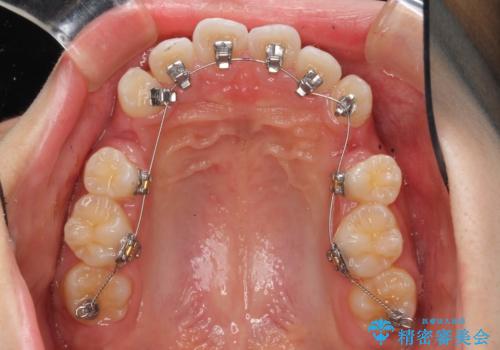

ハーフリンガル 半分裏側矯正による上下前突の抜歯矯正治療

- 矯正装置

- ハーフリンガル

- 上下左右4本の第1小臼歯を抜歯する、抜歯矯正を計画した。

抜歯矯正により前歯の位置が後ろに下がり、わずかではありますが、口元に改善がみられ、歯並びもきれいに整いました。